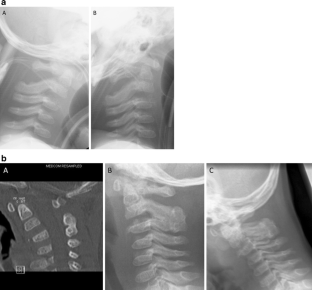

Via a posterior midline approach, the lamina of C2 and C3 was conflated in a modified sublaminar wiring technique using non-resorbable sutures, sparing the ossification zones of the vertebral arches. Postoperative immobilization in a halo vest facilitated bony fusion of the laminae at C2/3 without lordotic displacement of the cervical spine.